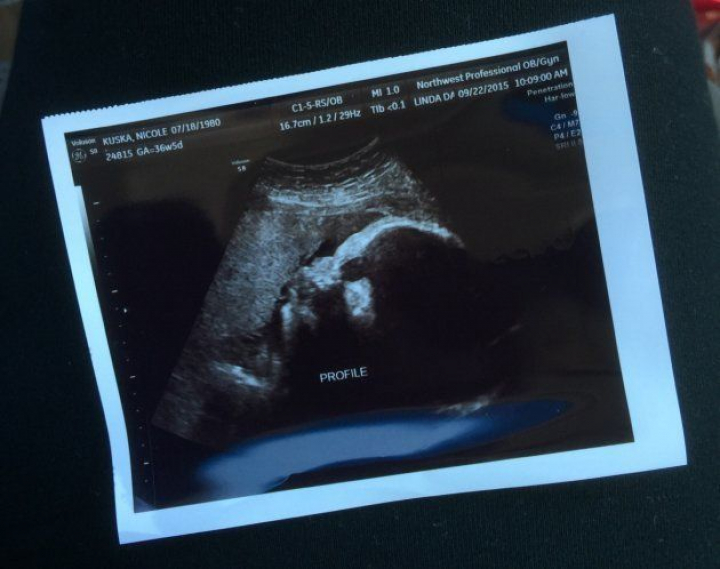

"Cuando elegí la agencia de subrogación, tuve que mandarles el historial médico de mis tres embarazos. También pasé un examen de salud mental y una entrevista personal. Y vinieron a casa a hacer una inspección. Cuando encontraron una pareja que quería ser padres, tuve que hacerme más pruebas médicas, incluida un ultrasonido para comprobar el estado de mi útero".

La pareja española viajó a Estados Unidos un mes después de aquel primer contacto por Skype. Se conocieron en persona en la agencia que había tramitado todo el proceso. "Ese día", cuenta Nikki, "sentí que podíamos haber estado hablando durante horas. Fue todo muy sencillo. Luego volvieron a EEUU para la prueba de ultrasonido que me hicieron en la semana 20 de embarazo y también fue estupendo. Vinieron a casa y, por primera vez, estuvieron con mis hijos. Salimos a Chicago a comer pizza y luego los llevamos a un partido de fútbol de mi marido".

Raúl nació el 13 de octubre de 2015. Pesó tres kilos y midió 51 centímetros.